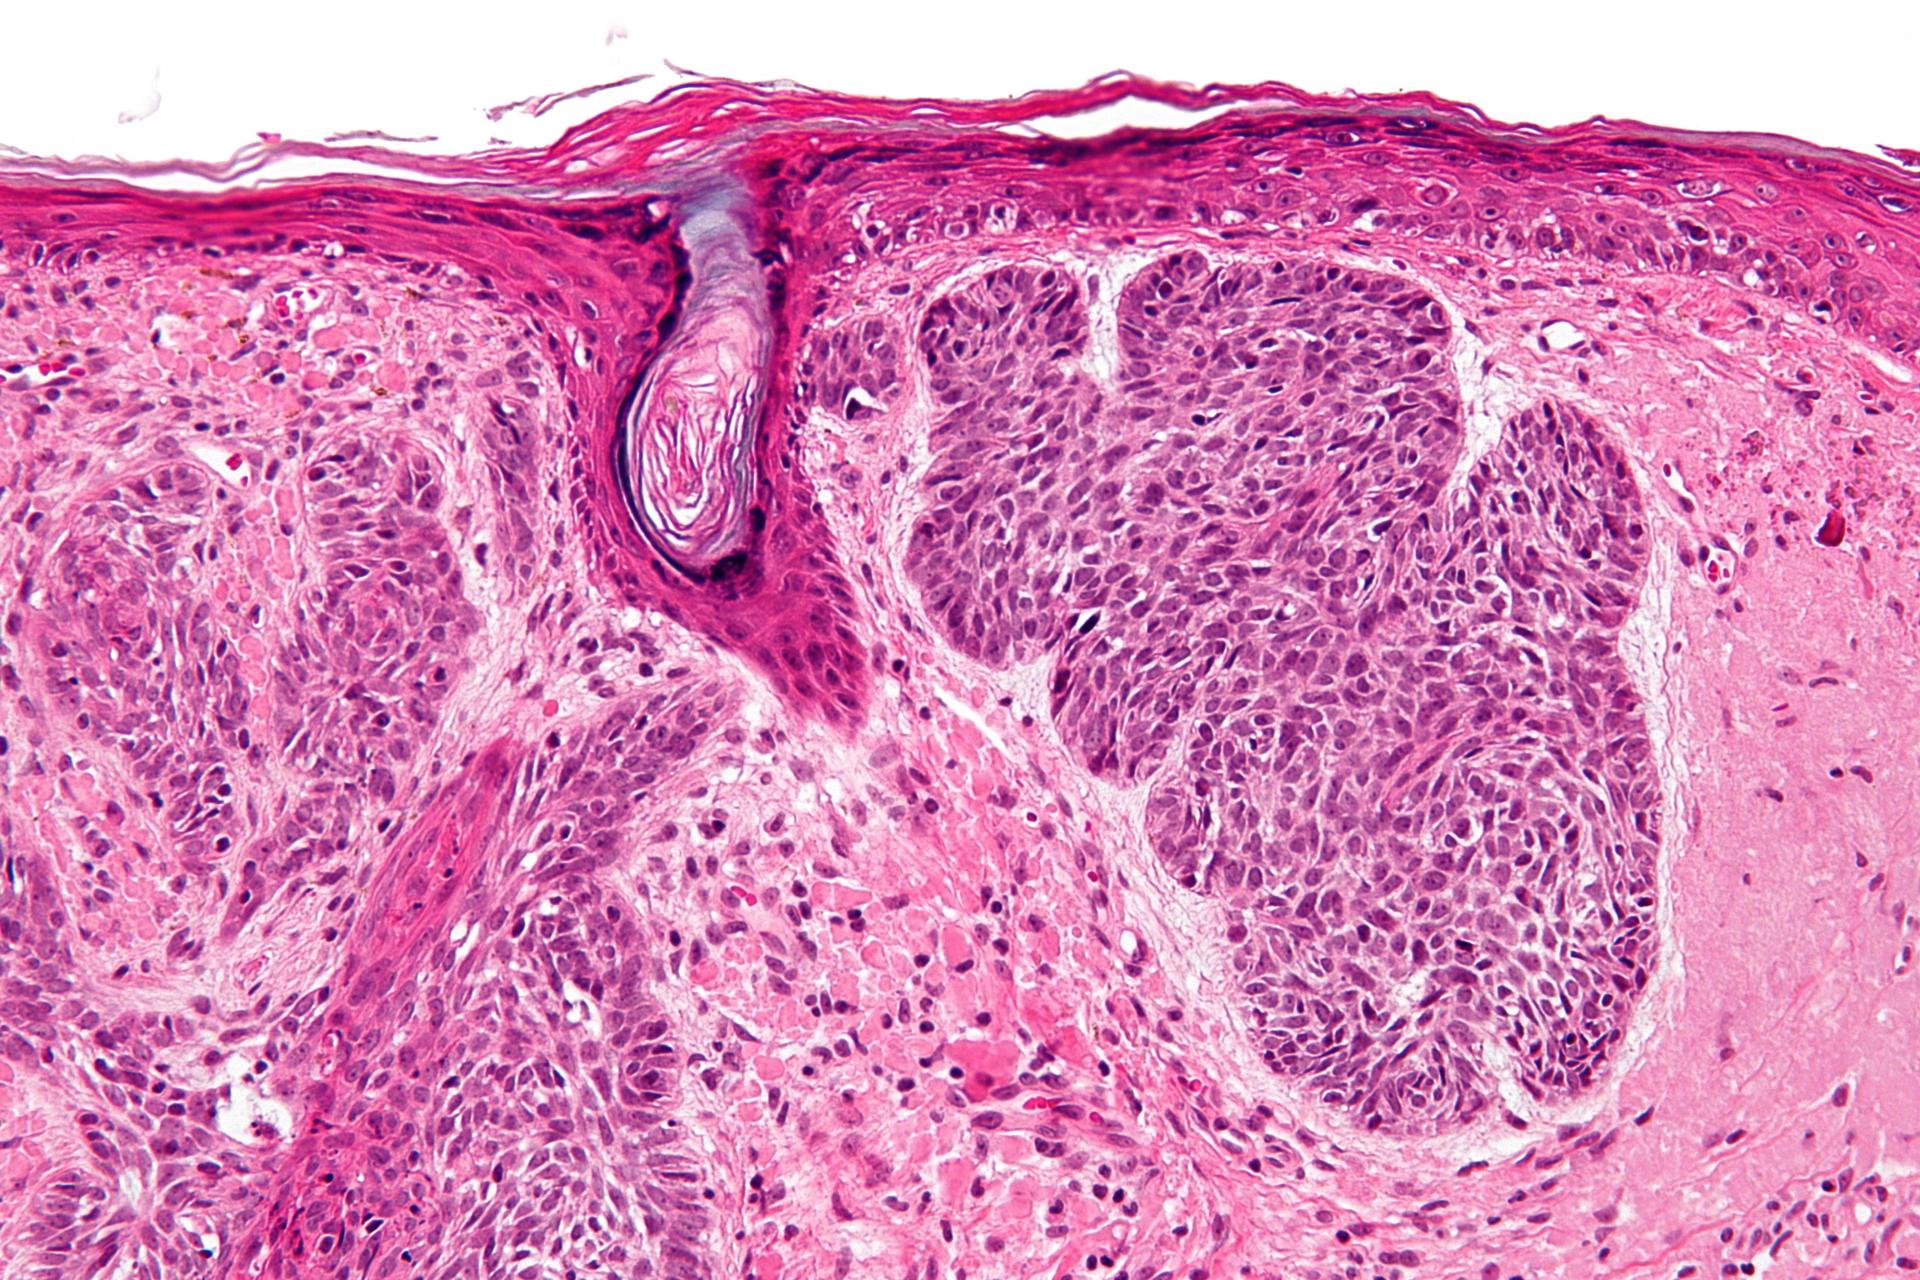

Фото раковой шишки на лице

Одной из наиболее распространенных локализаций раковых шишек является лицо. На фото вы можете увидеть различные типы раковых шишек, такие как базалиома, плоскоклеточный рак и меланома. Обратите внимание на характерные признаки каждого типа раковой шишки, такие как изменение цвета, формы и размера.